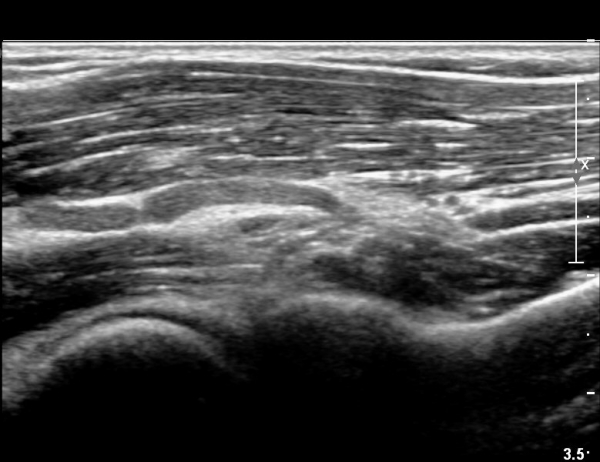

ÆÈ²ÞÄ¡ ¾Õ, Èİñ°£½Å°æ Ⱦ´Ü¸é °Ë»ç¿¡¼ Èİñ°£½Å°æÀÇ ºÎÁ¾ÀÌ °üÂûµÇ°í (»çÁø 1),